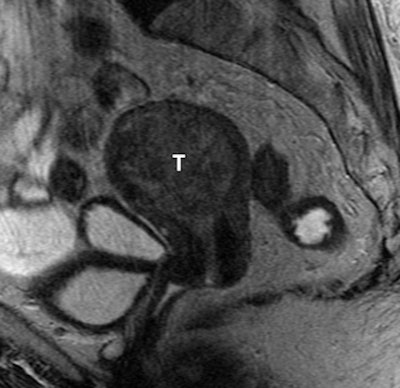

| MR image of an 83-year-old woman shows a large tumor (T) of intermediate signal intensity expanding the endometrial cavity. Pathologic diagnosis from the hysterectomy specimen was a clear cell carcinoma arising from the corpus. All images courtesy of Radiology. |